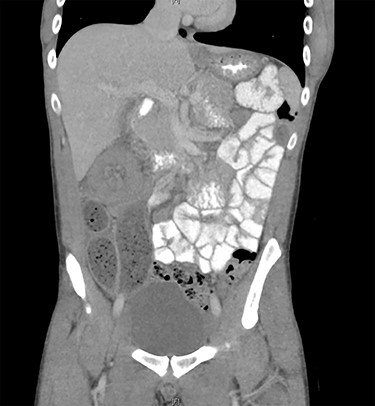

Due to diagnostic uncertainty, the patient underwent a computed tomography (CT) of the abdomen and pelvis with intravenous and oral contrast, which demonstrated ileo-colic intussusception, a distended ileum and no other features of bowel obstruction. Coronal and axial views of the CT scan showing the ileocolic intussusception are displayed in Figs 1 and 2, respectively.

CT of the abdomen and pelvis with axial view showing ileo-colic intussusception.